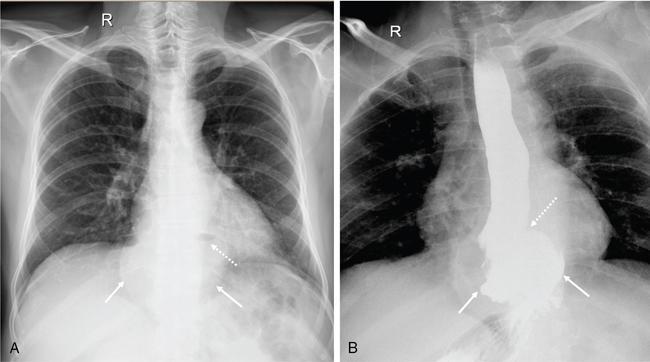

Swarup Nellore, Soumil Vyas, Ujwal Bhure, Ankit Jain, Richa Kothari, Daksh Mehta, Divya Kantesaria, Disha Lokhandwala, Karthik Ganesan The stomach is the most dilated portion of the gastrointestinal tract positioned between the oesophagus and the small intestine occupying the epigastrium, left hypochondrium and umbilical regions of the abdomen performing a multitude of functions including storage and mixing of food and controlling the passage of food into the intestine. Anatomically, the stomach is divided into the following parts (Fig. 8.2.1): the gastric cardia is the portion immediately adjoining the oesophageal opening into the stomach. The fundus is the dome-shaped part above the horizontal plane of the cardiac orifice which undergoes receptive relaxation and is the site of the autonomic pacemaker. The body is the largest part of the stomach extending from the cardiac orifice to the level of incisura angularis (notch like bend in the mid lesser curvature) containing majority of parietal cells (which secrete hydrochloric acid), chief cells (pepsinogen) and enterochromaffin-like cells (ECL). The pylorus is the tubular distal portion of the stomach which is further divided into the gastric antrum and pyloric canal. The pyloric antrum containing G-cells producing gastrin extends from the incisura angularis up to the pyloric sphincter which is an anatomical sphincter formed by concentric thickening of the circular muscle coat and encircles the narrow-slit like pyloric canal. The left dome of diaphragm and oesophagus lie superior to the stomach while the greater omentum and pancreas lie inferiorly. Spleen and liver lie on either side laterally while the transverse mesocolon is located inferolaterally. Diaphragm, greater omentum, left lobe of liver and anterior abdominal wall are anteriorly related to the stomach and contents of lesser sac including pancreas, spleen, splenic artery, transverse mesocolon, left kidney and adrenal gland lie posteriorly. The stomach is embryologically derived from the primitive foregut and is suspended anteriorly by the ventral mesogastrium and posteriorly by the dorsal mesogastrium. During development as the stomach rotates, the peritoneum grows and condenses to form perigastric ligaments, which contain blood vessels, lymphatics, lymph nodes, nerves and fat. The liver forms in the ventral mesogastrium, which develops into the falciform ligament, gastrohepatic ligament (GHL) and hepatoduodenal ligament (HDL). The spleen and pancreas form within the dorsal mesogastrium, which fuses with the posterior abdominal wall to form the gastrocolic ligament (GCL), gastrosplenic ligament (GSL) and splenorenal ligament (SRL). The perigastric ligaments are identified anatomically by the vessels contained in them (Fig. 8.2.2). The gastric cardia and lesser curvature of the stomach are attached to the inferior surface of liver by the lesser omentum by the gastrohepatic ligament respectively which contains the left and right gastric vessels. The inferior free edge of the gastrohepatic ligament extends inferiorly as the hepatoduodenal ligament between the porta hepatis and proximal duodenum gastrophrenic ligament extends between the stomach and the left hemidiaphragm. The gastrocolic ligament identified by the left and right gastroepiploic vessels, connects the greater curvature of the stomach to the anterior surface of the transverse colon. This ligament extends inferiorly as the greater omentum which is a double-layered peritoneum forming a drape anterior to the bowel loops. The gastrosplenic/lienogastric ligament bridges the posterolateral wall of the fundus and greater curvature along the proximal body of the stomach to the splenic hilum and contains the short gastric vessels. The gastrosplenic ligament is contiguous with the lienorenal ligament and both these structures constitute the lateral boundary of the lesser sac. Macroscopically the stomach shows a thick vascular mucosal lining in the form of longitudinal folds called gastric rugae. Microscopic layers of the stomach include mucosa, submucosa, muscularis externa and serosa. The mucosa includes surface mucus cells with simple columnar epithelium, gastric pits, gastric glands, lamina propria and muscularis mucosa. Submucosa includes connective tissue with submucosal Meissner’s plexus. Muscularis externa comprises three smooth muscle layers (longitudinal, circular and oblique) and Auerbach myenteric plexus. The outermost layer called serosa consists of loose connective tissue and visceral peritoneal lining. The arterial supply of stomach is constituted by the branches of celiac artery predominantly in the form of two anastomotic arcades along the lesser and greater curvature. Left gastric artery, a direct branch of the celiac trunk supplies the upper part of the lesser curvature while the lower part is supplied by the right gastric branch of the common hepatic artery arising at the upper border of pylorus. The left gastroepiploic artery, a branch of splenic artery, supplies the upper part of greater curvature and the inferior portion is supplied by the right gastroepiploic artery which is a branch of the gastroduodenal artery. The fundus additionally receives few small short gastric branches from the splenic artery. The veins follow the arteries in their nomenclature. Left and right gastric vein show direct drainage into the portal vein. The splenic vein derives flow from the short gastric and left gastroepiploic vein whereas the right gastroepiploic vein drains into the superior mesenteric vein. Pylorus can be surgically delineated by the prepyloric vein of Mayo lying on its anterior surface. Intrinsic nerve supply consists of the myenteric plexus of Auerbach and submucosal plexus of Meissner. Extrinsic nerve supply consists of sympathetic and parasympathetic components. Sympathetic nerve supply arises from T5 to T9 spinal cord segments supplying the celiac plexus via the greater splanchnic nerve. The plexuses then travel along the respective branches of celiac artery supplying the stomach. Parasympathetic nerve supply is derived from oesophageal plexus of vagus dividing into two vagal trunks. Right (posterior) vagus gives off the posterior gastric branch also called the criminal nerve of Grassi supplying the cardia and fundus of stomach. Right vagus then gives off a celiac branch and continues along lesser curvature of stomach as the posterior gastric nerve of Latarjet supplying the antrum, body and pylorus. Left (anterior) vagus gives off a hepatic branch then continues along the lesser curvature as the anterior nerve of Latarjet supplying the antrum, body and pylorus. Crow’s feet innervation to antropyloric area are important surgical landmarks preserved during highly selective vagotomy receiving branches from both major nerve trunks (anterior and posterior) at the incisura angularis. Anatomical lymphatic drainage is divided into three areas. Area I is the superior two-thirds of stomach draining via the nodes along left and right gastric vessels into the aortic nodes. Area II includes the right two-thirds of the inferior one-third which drains through the nodes along right gastroepiploic vessels via the subpyloric nodes into aortic nodes. Area III includes left one-third of greater curvature draining via short gastric and splenic nodes into suprapancreatic nodes and ultimately into aortic nodes. Gastric lymph node stations are divided into 4 levels with 16 lymph node stations: Paraesophageal nodes below the diaphragmatic hiatus (17) and above the diaphragmatic hiatus (18) are also included. The stomach first appears as a fusiform dilatation in the distal endodermal foregut in the 4th week of embryonic life. The dorsal and ventral mesogastrium suspend the developing stomach to the respective abdominal walls. Preferential growth along the dorsal border of the developing stomach leads to the formation of a convex dorsal border (greater curvature) and a concave ventral border (lesser curvature). The stomach subsequently undergoes a sequence of rotations. The first (90 degrees) clockwise rotation occurs around the longitudinal axis which brings the lesser curvature to the right and greater to the left. This rotation also brings the dorsal mesogastrium towards the left and ventral to the right creating a space behind the stomach called as the lesser sac or omental bursa. The second clockwise rotation occurs around the anteroposterior axis, with the caudal or pyloric part moving upwards and to the right while the cephalic or cardiac portion moves towards the left and slightly downward causing the stomach to assume its final anatomic position. This rotation causes the dorsal mesogastrium to bulge downwards and grow further to eventually become a double-layer apron called the greater omentum. The developing liver divides the ventral mesogastrium into the falciform ligament extending from the ventral abdominal wall to the liver with its lower free edge forming the ligamentum teres, the visceral peritoneum surrounding the liver and the lesser omentum with its two parts – the hepatogastric ligament and hepatoduodenal ligament. The dorsal mesogastrium gives rise to the redundant greater omentum, gastrocolic ligament, gastrosplenic ligament and lienorenal ligament. These perigastric ligaments help us in deciphering patterns of the spread of gastric malignancies and in taking decisions regarding their management and prognostication. These will be further explained in detail under the section of gastric malignancies. An abdominal radiograph is often the initial imaging test for evaluation of acute abdominal pain. The gastric bubble is seen below the left hemidiaphragm in situs solitus. Presence of gastric outlet obstruction may show a distended stomach with gasless small bowel. Hollow visceral perforation is diagnosed by free air seen under domes of diaphragm. Also, the presence and position of various tubes like the nasogastric tube can be confirmed using a radiograph. A fluoroscopic upper gastrointestinal (GI) examination is the radiological study of oesophagus, gastro-oesophageal junction, stomach, duodenum up to duodenojejunal junction by oral administration of contrast. Barium sulphate is a good contrast medium for GI studies as it is radio-opaque, non-absorbable, inert to tissues and can be used for double-contrast studies. Patient should be nil by mouth at least 4 hours prior to the examination. In a single contrast examination, the emphasis is on mucosal relief, luminal distention with contrast material and compression. In the erect position, a small amount of contrast is given to swallow while the oesophagus is visualized under fluoroscopy. The table is then made horizontal and the patient is rotated in a clockwise manner as seen from the foot end of the patient, thus ensuring good coating of the stomach mucosa. Mucosal relief images are then obtained in supine and prone positions to demonstrate the mucosal fold pattern and possible filling defects. After giving some more contrast, the patient is turned oblique with the right side dependent and spot images of the duodenal cap and C loop are taken both in distended and empty states. The patient is again positioned erect and more images of duodenal cap and loop are taken. Further contrast is given to optimally distend the lumen and assess for possible contour abnormalities, wall rigidity and strictures. Compression techniques help assess for filling defects and lesions, in the compressible areas of the stomach. Images are taken in multiple positions – supine, prone, right anterior oblique, right lateral, left posterior oblique in recumbent and right anterior oblique in erect position. Gastric peristalsis and emptying can be observed at fluoroscopy. Advantages of the single contrast technique are that it can be performed quickly, well-tolerated and requires less patient cooperation as compared to double-contrast studies. It can even be performed in physically debilitated patients. Barium is contraindicated in suspected cases of perforation, aspiration, fistula or recent GI biopsy. Single contrast examination can be performed using water-soluble iodinated contrast media in these cases and immediate postoperative patients. Earlier, ionic contrast like Gastrograffin was used. However, due to its high osmolarity, nowadays, non-ionic contrast is preferred as it causes less electrolyte imbalance due to its low osmolarity. Also, it delineates the GI tract very well due to less dilution. Double-contrast studies provide better evaluation of the mucosa than do single-contrast studies. Here, the emphasis is on coating the mucosa with barium and distending the lumen with gas. A well-performed double-contrast study is biphasic and also incorporates some single-contrast techniques. The initial part of the examination is the same as a single contrast examination to obtain the mucosal relief images. Then, gas-forming powder that produces carbon dioxide within the stomach lumen is given with more barium. With the double-contrast technique, the mucosa is coated with a high-density barium suspension and the lumen distended with gas. The patient is rotated in a clockwise manner as seen from the foot end of the patient, thus ensuring good coating of the stomach mucosa. Spot images of the distended stomach are taken followed by the duodenal cap and loop in oblique right-side dependent position. Patient is brought back to erect position erect and more images of stomach, duodenal cap and loop are taken. Further contrast is given to distend the lumen. Residual fluid or food debris in the stomach impairs stomach coating, and lack of adequate coating may preclude visualization of lesions. In addition, optimal gaseous distention is important as underdistention will cause a false appearance of abnormally thickened, and overdistention can obliterate abnormal folds. With normal gastric anatomy, the gastric fundus is best visualized in the upright left-posterior-oblique position, the body in the supine anteroposterior position and the antral-pyloric region in the supine left-posterior-oblique position. The normal gastric mucosal surface should be smooth on double-contrast studies. Areae gastricae appear as reticular networks of polygonal tufts which, owing to the presence of barium in the narrow intervening grooves, are coated with white lines. These are seen most often in the antrum or body of the stomach but can also be seen in the fundus. Areae gastricae are identified on double-contrast studies in 70% of patients and are seen more often in elderly patients. Polygonal tufts should normally range in size from 2 to 3 mm in the antrum and 3 to 5 mm in the body and fundus. Normal gastric folds are more prominent in the proximal to mid stomach and more undulating along the greater curvature as compared with the lesser curvature. Antral folds should be typically effaced with the double-contrast technique. Gastric cardia is characterized by three or four stellate folds radiating from a central point at the gastro-oesophageal junction; this is known as the cardiac rosette and is best visualized in the supine right-lateral position. Ultrasonography (USG) is the modality of choice to visualize hypertrophic pyloric stenosis in infants. Although USG does not play much of a role in adults for imaging of stomach due to reflection of sound waves by air, luminal distension with water may enable to identify mucosal – submucosal pathologies and to assess perigastric relationships in pathologies. CT can not only evaluate the location and anatomy of the stomach, but also provide additional information about the relationship of the stomach to surrounding structures. An optimal CT examination of the stomach includes good stomach distension with a well-visualized wall. Gastric distention can be achieved by the oral administration of negative or positive luminal contrast. Positive contrast agents include a 1%–2% barium suspension or a 2%–3% solution of a water-soluble iodinated contrast agent. Water-soluble agents should be used in cases of suspected perforation. Positive agents provide a bright lumen with better identification of luminal encroachment or diverticula but may limit detailed evaluation of gastric wall enhancement. Positive contrast also may not mix well with gastric contents, producing a pseudotumor appearance. On the other hand, neutral or negative contrasts agents, usually water, produce a low attenuation lumen which allows for more detailed evaluation of the gastric wall and its enhancement pattern following intravenous contrast and is preferred for three-dimensional imaging. Multidetector CT with thin collimation allows for postprocessing in any orthogonal plane. The CT data of the stomach can be manipulated to simulate endoscopic images (virtual gastroscopy). This display technique accentuates the stomach wall and folds. Prior to evaluating the stomach with CT, oral contrast is administered at repeated intervals as well as immediately prior to scanning. Multiphasic scanning after intravenous contrast may be employed at 25–35 seconds (late arterial), 55–75 seconds (venous phase) after contrast injection. Normally, the gastric wall may enhance to approximately 120 Hounsfield Units after intravenous contrast administration. The mucosa may enhance more than the relatively lower-attenuation muscularis propria. Abnormal enhancement of the wall can highlight pathologic processes. The CT appearance of the stomach also depends upon the degree of distention. When well distended, the body and fundus is less than 5 mm thick, though the normal antrum may appear slightly thicker. The presence and pattern of wall enhancement, degree and location of wall thickening, and length of an involved segment may be assessed. Comprehensive MRI examination of the stomach and duodenum by the combined use of T2-weighted single-shot and T1-weighted gradient echo (GRE) – with and without fat suppression, and gadolinium-enhanced 3D GRE helps to detect the spectrum of gastric diseases on MRI. These sequences minimize artefacts from bowel peristalsis, increase the sensitivity of detection of peritoneal and serosal disease by suppressing the high signal of intra-abdominal fat, widen the dynamic range of abdominal tissue signal intensities and distinguish between intraluminal bowel contents and bowel wall. The gastric rugae are well seen on T2-weighted single-shot spin-echo images and their enhancement appears as bands of enhancing tissue arranged perpendicular to the external contour of the gastric wall. The normal gastric wall enhances more intensely than other segments of bowel on immediate postgadolinium SGE images. Water is frequently used as an oral contrast agent when imaging the upper GI segment-stomach and duodenum. Noninvasive dynamic study for assessment of gastric motor function and wall motility can also be done using MRI for diagnosis of gastroparesis. Gastric emptying scintigraphy (GES) is a well-established radionuclide procedure to evaluate patients with suspected gastric motility disorder, more so for non-invasive assessment of gastroparesis in patients with symptoms of postprandial fullness, nausea, vomiting, abdominal pain, bloating, early satiety, loss of appetite, as well as weight loss. Gastroparesis, commonly seen in diabetics, is a condition that affects the normal spontaneous movement of the gastric muscles, leading to impairment of gastric motility, because of which the stomach cannot empty itself of food in a normal fashion and time. GES can also provide useful information with regards to assessment of impaired gastric motility in patients with GERD (gastro-oesophageal reflux disease) unresponsive to routine therapy, diabetics with poor glycemic control, and also in patients with colonic inertia who are being considered for colectomy (since benefits of colectomy are mitigated in patients with concurrent impaired gastric emptying). On the other hand, GES is also useful for assessment of rapid gastric emptying (GE), which is a major factor in dumping syndrome, often seen post peptic ulcer surgery, with or without vagotomy. The solid or liquid component of a meal is radiolabelled with a radiopharmaceutical, which is consumed by the patient and subsequently measured gastric radioactive counts by scintigraphy correlate with the volume of the meal remaining in the stomach. Solid-phase GES is used for the evaluation of gastric motility disorder/gastroparesis. Liquid-phase gastric emptying is generally not clinically useful since it is often in the normal range in spite of deranged emptying for solids even with severe gastroparesis. The preferred radionuclide meal for the gastric emptying scintigraphy includes egg-white radiolabelled with 0.5–1.0 mCi of Technetium-99m (99mTc) [approximate caloric value of 255 kcal]. Two large eggs (egg-whites), two slices of bread, fruit jam, water (120 mL approximately), and the radiopharmaceutical (0.5–1.0 mCi of 99mTc–sulphur colloid). For patients allergic, to eggs, alternative meals like oatmeal or Liquid Ensure nutrient supplement can be used. Reporting should include the percentage of radiotracer retained in the stomach at defined time intervals. The normal reference values for comparison are as follows: Grading the severity of the delay in gastric emptying based on gastric retention at 4 hours of the study: Gastro-oesophageal reflux (GER) is a common condition in infants and children, wherein there is reflux of stomach contents into the oesophagus, due to possible incompetence of gastro-oesophageal sphincter, which can lead to development of symptoms like regurgitation, heartburn, cough and dyspepsia. Children can present with recurrent respiratory infections, iron deficiency anaemia and failure to thrive. It is often a self-limited process in infants and children which usually resolves by 12–18 months of age. On the other hand, gastro-oesophageal reflux disease (GERD) is a chronic pathological process which can be troublesome. Scintigraphic evaluation of gastro-oesophageal reflux, popularly known as ‘milk scan’, is an established imaging modality and has sensitivity of 75%–100%. This radionuclide test for gastro-oesophageal reflux is physiological and quantitative and commonly used for diagnosis in neonates and infants. Four hours fasting is preferred. A liquid meal consisting of formula, milk, or orange juice mixed with the radiopharmaceutical is administered either orally or by nasogastric tube. 99mTc–sulphur colloid. Dose: 0.2 to 1 mCi. After administering the liquid meal and allowing burping, the baby is positioned supine under the gamma camera detector head, including chest and upper abdomen in the field of view. A radioactive marker can be placed at the mouth. Anterior serial dynamic planar images are acquired for around 60 minutes with a framing rate of 5–10 seconds per frame. Delayed anterior static image of the chest may be acquired additionally. The acquired frames are reviewed in cinematic display for visual estimation and to look for reflux of the radiotracer into the oesophagus. Reflux is seen as distinct spikes of radiotracer activity into the oesophagus. For quantitative estimation, the volume of each episode of reflux, frequency of episodes and rate of reflux clearance from the oesophagus are taken into consideration. Percentage of reflux is calculated by drawing an ROI over the oesophageal spike of radiotracer activity and the counts are calculated and expressed as a fraction of the gastric activity counts. Values greater than 5% are suggestive of reflux. Semiquantitative evaluation grades each reflux event: Based on this, four categories can be formulated: The greater the number of high-level reflux events and the longer they last, more severe is the gravity of the problem. Pulmonary aspiration should also be looked for, though the sensitivity of detection is poor. Liquid gastric emptying can be evaluated during the same study up to 2 hours. Normal values for liquid gastric emptying are: Endoscopy is the preferred examination to evaluate for majority of the upper GI symptoms. It is very sensitive in detecting mucosal lesions and simultaneously, biopsies can be taken. In cases of upper GI bleed, endoscopy can not only detect the site and cause of the bleed, but also further treatment like adrenaline/sclerosant injection or ligation can be done. EUS can provide detailed assessment of the 5 layers of the gastric wall and is thought to be the most accurate non-surgical method for local tumour staging (Fig. 8.2.9). For subepithelial (submucosal) gastric lesions, EUS can assess the echogenicity of a lesion, the exact layer of the gastric wall which is involved (accurate T-staging of a tumour) and assess for the presence of blood flow with Doppler ultrasound to help ascertain the likely aetiology. EUS-guided fine needle aspiration may also provide additional diagnostic information. Hiatus hernia is a common positional abnormality of stomach, characterized by herniation of abdominal contents, commonly the gastro-oesophageal junction and stomach, into the mediastinum above the diaphragm through a widened oesophageal hiatus. The oesophageal hiatus is an elliptical opening with complex anatomy formed by the right and left crus of the diaphragm. However, the most common anatomical description is of the right crus splitting into two bundles, the right and left, which form a sling encircling the distal oesophagus and may be reinforced by the left diaphragmatic crus. The distal oesophagus is typically anchored to the oesophageal hiatus by a main restraining structure which is the phrenicoesophageal ligament/membrane (the fascia of Laimer) which is a condensation of endo-thoracic and endo-abdominal fascia and this membrane circumferentially inserts into the oesophageal musculature in close proximity to the squamocolumnar junction (SCJ). The ligament maintains the competence of the oesophageal hiatus and prevents rostral herniation of the gastro-oesophageal junction and stomach. During normal physiological swallowing, the longitudinal layer of the oesophageal muscularis propria contracts with associated oesophageal shortening and stretching of the phrenicoesophageal ligament/membrane resulting in the transient elevation of the oesophagogastric junction and portion of the stomach above the hiatus. At the end of the swallowing mechanism, the elastic recoiling of the phrenicoesophageal ligament/membrane restores the migrated segment to its normal position. With ageing-related wear and tear, the ligament becomes lax with progressive depletion of elastin fibres resulting in proximal migration of the gastro-oesophageal junction and stomach. Other potential risk factors of fibromuscular degeneration are caused by increase in the intra-abdominal pressure as occurs in obesity and pregnancy. The majority of the symptomatic cases of hiatal hernia present with the clinical symptoms of gastro-oesophageal reflux disease (GERD) with most characteristic manifestations of acid regurgitation, heartburn, dysphagia, epigastric or chest pain and even chronic iron deficiency anaemia. Large hernias may also present with early satiety. Conventionally, hiatus hernias are classified into sliding and paraesophageal varieties. The current comprehensive anatomic classification has evolved to include a categorization of hiatal hernias into Types I–IV and is necessary especially regarding the treatment approach, as indications for the surgical method are quite different between sliding and paraesophageal hernias. Majority of hiatus hernias (95%) are sliding hiatus hernias (type I), the remaining type II–IV hernias as a group are referred to as paraesophageal hernias (PEH), with more than 90% of these comprising type III, and the least common being of type II. The assessment of hiatus hernia can be done by various modalities including radiological, manometry and endoscopy studies. The diagnosis of a large hiatus hernia is straightforward, however, identifying a small one is challenging due to mobility of the gastro-oesophageal junction during physiological process like deglutition and respiration. According to the SAGES Guidelines, only those investigations which will alter the clinical management of the patient should be performed. Radiological investigations are usually indicated for diagnosis and presurgical evaluation. Plain chest radiographs demonstrate opacity within the chest typically in the midline overlapping the cardiac shadow or paramedian location (Fig. 8.2.14A), with or without an air-fluid level. Barium swallow radiography is still considered an easy tool for diagnosis of hiatus hernia and provides essential information about the size, location, motility dysfunction, stricture secondary to GERD and stenosis. The evaluation of hiatus hernia requires understanding of anatomical radiographic landmarks like phrenic ampulla, A ring and B ring (or Schatzki’s ring) on a barium study (Fig. 8.2.14B). The phrenic ampulla is a globular structure seen above the diaphragm and below the tubular oesophagus during a contrast swallow. The A ring represents a muscular ring visible at the upper margin of the phrenic ampulla and physiologically corresponds to the highest-pressure zone within the lower oesophageal sphincter, this is often seen as a transient indentation on the oesophageal lumen. The B ring identified in about 15% of individuals, representing the mucosal ring corresponds to the squamocolumnar junction (Z line) and divides the phrenic ampulla into the oesophageal vestibule (A ring to B ring) and the sliding hiatus hernia (B ring to the stomach below the diaphragm). The B ring is a persistent constriction which is not usually not more than 2–3 mm and despite mucosal, can sometimes be symptomatic and require dilatation. By convention, there must be a distance of 2 cm or more between the B ring and the hiatus, to call it a hiatus hernia as physiological migration up to 2 cm is known in normal individuals. Although not reliable, barium studies may also provide information about a short oesophagus, which is identified as a tubular straightened oesophagus with the oesophagogastric junction fixed far above the diaphragm and may be stenotic, the intrathoracic herniated stomach revealing a more elongated funnel/bell – shaped configuration. Cine fluoroscopy provides further additional information about the bolus transit through gastro-oesophageal junction. The major drawbacks of the procedure are non-visualization of B-ring in majority of the cases, radiation exposure, barium/iodine hypersensitivity, contraindication in pregnancy and increase risk of aspiration in paraesophageal hernia causing pneumonitis. Computed tomography (CT) scan is not routinely advised for the primary diagnosis of hiatus hernia but is indicated in cases of suspected complications like volvulus in paraesophageal hernia, obstruction, perforation and strangulation. Multi-slice CT with reconstruction in sagittal, coronal planes and 3D reformations have increased the sensitivity of CT in detection of hiatal hernia. Oesophagogastroduodenoscopy gives added advantage of real-time visual assessment of the mucosa of the oesophagus, stomach and duodenum. The common diagnostic criteria in endoscopic is proximal migration of gastro-oesophageal junction by >2 cm. Endoscopy can also determine the presence of erosive esophagitis or Barrett’s oesophagus. Further, the inability or difficulty of negotiating the scope into duodenum in the presence of a large hiatal hernia is diagnostic of paraesophageal hernia with volvulus. Evaluation of gastric viability is also important in patients undergoing emergency surgery for incarcerated hernias. The disadvantage of the procedure is lack of reproducibility; retching or belching of the patients during examination which can alter the location and anatomy of GEJ and excess air insufflation of the stomach which may exaggerate the size of the hernia. Oesophageal manometry is measured at the level of the diaphragmatic crura, however, manometric landmarks differ from that of barium study and endoscopy, and identified by pressure inversion point. In patients with a paraesophageal hiatal hernia, placement of the manometry catheter across the lower oesophageal sphincter and below the diaphragm can be difficult. The procedure is planned before surgery to exclude motility disorders like achalasia and to verify the integrity of oesophageal peristalsis. pH testing is not essential in the diagnosis of a hiatal hernia, but is necessary for a quantitative analysis of reflux in a case of hernia which can be relieved by antireflux surgery. Confirmation of abnormal gastro-oesophageal reflux on upper endoscopy, or increased oesophageal acid exposure on pH monitoring is necessary prior to operative intervention in patients with a sliding hiatal hernia. Nuclear medicine studies, transoesophageal echocardiogram (TEE) and endoscopic ultrasound (EUS) can also demonstrate hiatal hernias but are not routinely used for diagnosis. The main aim of treatment in symptomatic patient is to reduce the acid reflux. Lifestyle modifications are the first line of management and include weight loss, elevating the head of the bed preferably by 8 inches during sleep, avoidance of meals for atleast 2–3 hours before bedtime and elimination of ‘trigger’ foods. According to the SAGES Guidelines updated in April 2013, the treatment protocols are provided on the basis of types of the hiatus hernia. Type I (sliding) hiatus hernia are usually managed with proton pump inhibitors for 8 weeks, once or twice daily depending on the symptoms. Other alternatives are H2 receptor antagonists and antacids. If the patient is not relieved symptomatically by medication, surgical repair like laparoscopic fundoplication (Nissen or Toupet) can be done. Steps of fundoplication comprise surgically relocating the gastro-oesophageal junction below the diaphragm, maintaining an oesophagogastric angle to prevent gastro-oesophageal reflux, constructing a gastric wrap around the distal oesophagus to support the distal oesophageal sphincter and increase its resting pressure, and finally approximate the diaphragmatic hernia to narrow the widened hiatus. In all symptomatic Type II, III and IV hiatus hernia, surgical repair is strongly recommended as the primary treatment, particularly those with acute obstructive symptoms or which have undergone volvulus. Routine elective repair of completely asymptomatic paraesophageal hernias may not always be indicated and determinants for surgery should include the patient’s age and co-morbidities. These fundoplication surgeries are described later in the text. Gastric volvulus is an uncommon entity and characterized by abnormal rotation of the stomach (usually >180°) along the long or short axis, leading to variable degree of gastric obstruction, which can be of a closed-loop type resulting in strangulation. The exact incidence of gastric volvulus is unclear as patients with a chronic presentation may never be diagnosed.2 Approximately, 10%–20% cases of gastric volvulus occur in children less than 1 year, while the other 80% cases are detected in adults, of which 80%–90% are often encountered in the fifth decade of life.3 No significant predilection is seen with either sex or races. Gastric volvulus can be classified on the basis of aetiology, axis of rotation and duration of onset. While classification based on axis of rotation by Singleton is widely accepted and more relevant to the radiologist, classification based on duration of onset of symptoms is more relevant in clinical assessment. On the basis of axis of rotation (Fig. 8.2.15), gastric volvulus is divided into organoaxial volvulus, mesenteroaxial volvulus and the rarest combined/mixed type. Organo-axial volvulus, by far, the most common type of gastric volvulus, encountered often in the elderly, is characterized by rotation of the stomach along its long axis, that is, cardio-pyloric axis, and resulting in an ‘inverted stomach’ with a horizontal orientation, in the form of anterosuperior displacement of the antrum and posteroinferior rotation of the fundus, so that the greater curvature is displaced superiorly and lesser curvature caudally in the abdomen (Fig. 8.2.16). The site of obstruction in this type of volvulus is at the cardia or at pylorus. It has a higher predisposition towards strangulation and ischaemia. Organo-axial volvulus also shows association with the paraoesophageal hernia or diaphragmatic defects, which allows abnormal movement of the stomach along the long axis. If the degree of rotation is less than 180 degrees, the patient may have an incomplete or partial volvulus which is not completely obstructing and may be asymptomatic; it may be more appropriate to describe it as organo-axial position rather than volvulus. Mesenteroaxial volvulus is less commonly encountered (30%) and accounts for about 29% of cases, is reported more often in young adults or children. It occurs when the stomach rotates around its short (transverse) axis, that is, line connecting the midpoint between the lesser curvature and the greater curvature of the stomach, leading to a vertically oriented stomach, with anterior rotation of the pylorus, antrum and resultant displacement of the antrum above the gastro-oesophageal junction (Figs 8.2.17 and 8.2.18). The site of obstruction is usually at antropyloric region. It is usually not associated with a diaphragmatic defect and is often idiopathic. The third and rarest type of gastric volvulus is the combined type when the stomach shows both rotation along the short and long axes. Based on aetiology of rotation, gastric volvulus can be subdivided into either primary or secondary. Primary gastric volvulus representing 25%–30% of the cases, is more common in the adults. It occurs in the subdiaphragmatic location due to abnormality in the gastric fixation, exclusively because of disruption, laxity or absence of the gastric ligaments which anchor the stomach in place. These ligaments namely the gastrohepatic, gastrocolic, gastrophrenic, gastrosplenic and gastropancreatic ligaments, along with gastro-oesophageal junction and pylorus, provide anchorage and fix the stomach in place intra-abdominally, and prevent abnormal rotation of the mesentery. The primary gastric volvulus usually presents with the mesenteroaxial type of anatomical configuration. Around 70% of patients present with secondary gastric volvulus occurring due to abnormal rotation around the lead point formed by associated disease. The most common association of gastric volvulus is seen with paraoesophageal hiatus hernia. Other causative factors of volvulus include congenital or traumatic diaphragmatic hernia, diaphragmatic paralysis, eventration, connective tissue disorders, previous surgery, adhesions, peptic ulcer, neoplasm, splenomegaly or absence of the spleen and colonic overdistension. On basis of clinical presentation and speed of onset, gastric volvulus can be acute, subacute or chronic. Acute gastric volvulus is a surgical emergency and usually presents with sudden onset epigastric pain, distension, non-bilious vomiting or severe retching, depending on the degree of obstruction. The Borchardt triad of acute volvulus comprises severe epigastric pain and distention, retching but inability to vomit, and difficulty or impossibility of passing a nasogastric tube and may be observed in 70% of cases. Other symptoms include hematemesis due to mucosal sloughing in stomach gangrene or mucosal tear due to retching, dysphagia and dyspnea. Even after prompt treatment, mortality of acute gastric volvulus can be up to 30%–50%, likely secondary to gastric ischaemia, perforation or necrosis resulting from severe gastric obstruction (closed-loop obstruction) causing vascular compromise, making it a life-threatening surgical emergency. Chronic gastric volvulus represents spectrum of diseases from long-standing partially obstructed volvulized stomach with incomplete gastric obstruction on the one side, and intermittent volvulus of stomach with recurrent episode of acute symptoms as the other presentation. Chronic gastric volvulus usually presents with intermittent complaints of vague epigastric pain, non-bilious vomiting, dysphagia or early satiety, dyspepsia and sometimes regurgitation. Due to nonspecific clinical symptoms, diagnosing gastric volvulus is very challenging on the first instance and requires a high clinical suspicion. Diagnostic imaging, along with clinical findings are usually required to achieve the correct diagnosis, and also plays major role in excluding the other common differential diagnosis, like pancreatitis, cholecystitis or pneumonitis etc. The diagnostic modalities useful in suspected cases of gastric volvulus are plain radiographs, upper gastrointestinal contrast (barium) studies, computed tomography and upper gastrointestinal endoscopy. Plain chest and abdominal radiographs may reveal a radiolucent hollow viscus, with or without an air-fluid level, in the chest (when associated with PEH) or upper abdomen. The presence of a nasogastric tube may assist in identifying a malpositioned stomach, and administration of contrast via the nasogastric tube may be confirmatory in this regard. Furthermore, chest radiographs may identify evidence of underlying anatomic abnormalities predisposing to gastric volvulus, including elevated hemidiaphragm due to phrenic nerve palsy or diaphragmatic eventration and rib fractures suggesting prior thoracoabdominal blunt trauma. The plain radiographs may show two air-fluid levels in the antrum and fundus, or a single air bubble with no additional luminal gas in the supine position. A retrocardiac air-fluid level may be seen secondary to hernia and presence of intramural air (gastric emphysema) can be visualized as a radiolucent stripe in the gastric wall. At times a large hiatus hernia may be complicated by volvulus (Fig. 8.2.19). Passage of orally administered contrast like barium can demonstrate the anatomy and also assess the degree of obstruction. As mentioned above, the position of the gastric curvatures and the gastro-oesophageal junction are useful in differentiating the anatomical subtype of volvulus. Computed tomography may be more feasible in an acute emergency setting in order to identify abnormal gastric position, axis and multiplanar reconstructions, especially in the coronal plane, can well elucidate the findings and an associated complication like ischaemia. CT has an overall 90% accuracy in the diagnosis with identification of gastro-oesophageal junction and pylorus lying in close proximity to each other and the transition point at the pylorus known to have 100% sensitivity and specificity. Abnormal antral folds may be seen secondary to the twisting. Stenosis at the neck of the hernia is the CT finding with the second-highest sensitivity (77%–80%) and specificity (94%–97%). CT findings of oedematous or hypoenhancing gastric wall, pneumatosis, pleural effusion or pneumoperitoneum, as indicators of gastric ischaemia are not common but specific when identified. An upper gastrointestinal endoscopy confers both diagnostic and therapeutic benefit, although it may establish the diagnosis in only 28%–45% patients and also, the endoscopic procedure may reduce the volvulus missing the diagnosis by an unwary endoscopist. However, it still remains the best method to detect mucosal ischaemia. Flexible endoscopy also has the advantage of placing a nasogastric tube as it may not be possible with a blind technique at the bedside in the setting of organoaxial volvulus and an obstructed gastro-oesophageal junction. Nasogastric decompression forms the initial management of gastric volvulus with emergent laparotomy or laparoscopy to assess gastric viability, resect gangrenous portion if any and perform de-rotation and gastropexy (fixation of the stomach to the diaphragm and/or the anterior abdominal wall) with or without gastrostomy with repair of secondary factors like paraoesophageal hernia. Erosions are focal shallow areas of ulcerations confined to the epithelium or lamina propria without extending through the muscularis mucosae into the submucosa. NSAIDs are the most common cause of gastric erosions while other incriminated factors include Helicobacter pylori infection, alcohol, viral infections, Crohn’s disease, stress and iatrogenic trauma. Erosions may be visible on double-contrast barium examination obtained with good mucosal coating, as multiple tiny 1- to 2-mm collections of barium, often with a surrounding mound of oedema appearing as a filling defect in the barium pool (Fig. 8.2.20). They are usually located in the gastric antrum and tend to occur along thickened folds.

Hiatus hernia